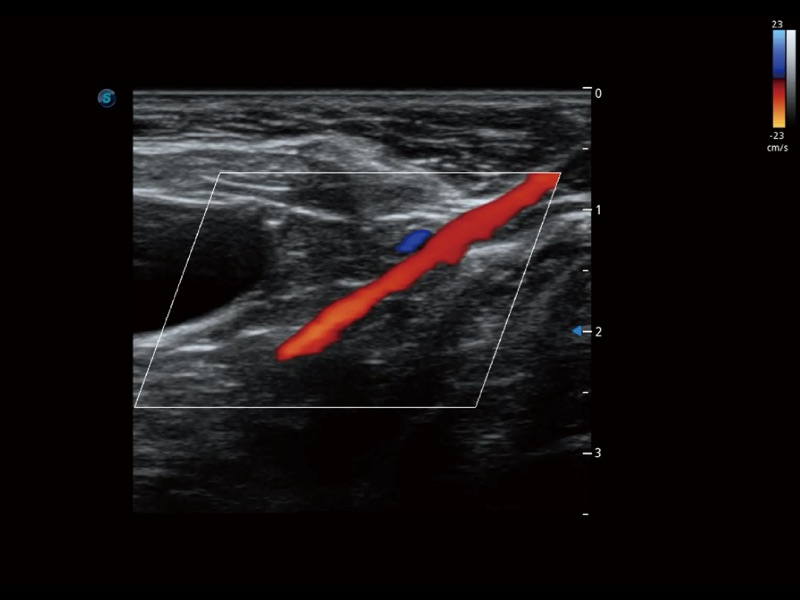

通过色彩血流和实时宽景相结合,可观察到完整的静脉或动脉的血流,方便医生检查。实时扫查过程中,如有任何操作失误也可以很容易地进行回扫擦除,而不会中断扫查。

通过创新的 Matrix E自适应滤波器和超长时间域算法,极大提升超低速微细血流的检出能力,同时更精准地滤除软组织和噪声信号,为兽用医生提供以往无法通过常规血流获得的疾病诊断信息。

为精细结构及组织边缘提供高清晰度的图像和更大的成像视野。帮助减轻医生的用眼疲劳,快速精准获得测量的数据。